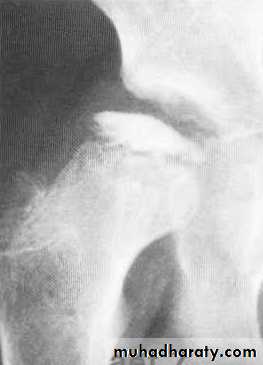

• Syringomyelia: usually shoulder

• Radiographic features

• Common to all types

• *Joint instability: subluxation or dislocation

• *Prominent joint effusion

• --- Hypertrophic type, 20%

• Marked fragmentation of articular bone

• Much reactive bone

• --- Atrophic type, 40°/0

• Bone resorption of articular portion

• --- Combined type, 40%